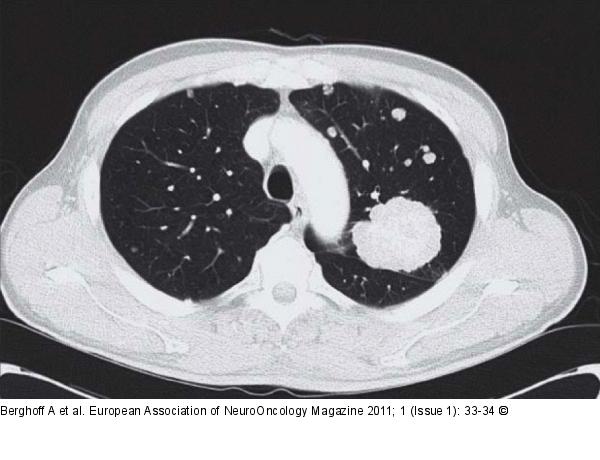

Figure/Graphic 3: Thoracic CT Thoracic CT with contrast agent. |